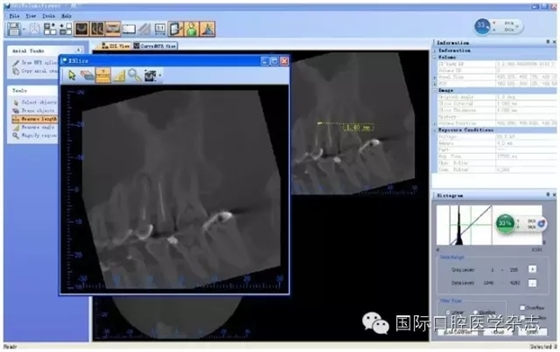

目前,對(duì)于分離器械周?chē)辣举|(zhì)厚度的評(píng)估以及取出后殘余牙本質(zhì)厚度的預(yù)測(cè)主要需借助影像學(xué)檢查,例如根尖片、錐形束CT(cone beamcomputed tomography,CBCT)圖像等。傳統(tǒng)的平行投照的根尖片無(wú)法反映三維立體結(jié)構(gòu),且往往存在解剖結(jié)構(gòu)影像的重疊,不利于臨床判斷,具有一定的局限性。多位學(xué)者[10]的研究表明:平行投照的根尖片會(huì)高估實(shí)際的牙本質(zhì)壁的厚度。一些學(xué)者[11-12]的研究表明:當(dāng)分離器械位于上頜第一磨牙近中根管時(shí),采用成角投照(21°)的拍攝技術(shù)與平行投照技術(shù)得到的X線(xiàn)片相比,能更準(zhǔn)確地評(píng)估牙本質(zhì)的厚度,為分離器械取出與否提供指導(dǎo)(圖4)。近年來(lái),CBCT在牙髓病學(xué)中的應(yīng)用越來(lái)越廣泛,由于CBCT能清楚地反映牙及牙根周?chē)M織的三維立體結(jié)構(gòu),為牙本質(zhì)厚度的評(píng)估與預(yù)測(cè)提供了可行性(圖5);因此,CBCT在器械分離的病例術(shù)前風(fēng)險(xiǎn)評(píng)估方面具有較好的應(yīng)用前景。

A、B:采用平行投照技術(shù)獲得的圖像,模擬取出分離器械后殘余牙本質(zhì)的厚度,分離器械分別位于根管口下3 mm和5 mm;C、D:采用成角投照技術(shù)獲得的圖像,模擬取出分離器械后殘余牙本質(zhì)的厚度,分離器械分別位于根管口下3 mm和5 mm。

圖 4 平行投照與成角投照拍攝技術(shù)對(duì)牙本質(zhì)厚度的評(píng)估

圖 5 使用CBCT評(píng)估分離器械周?chē)辣举|(zhì)厚度